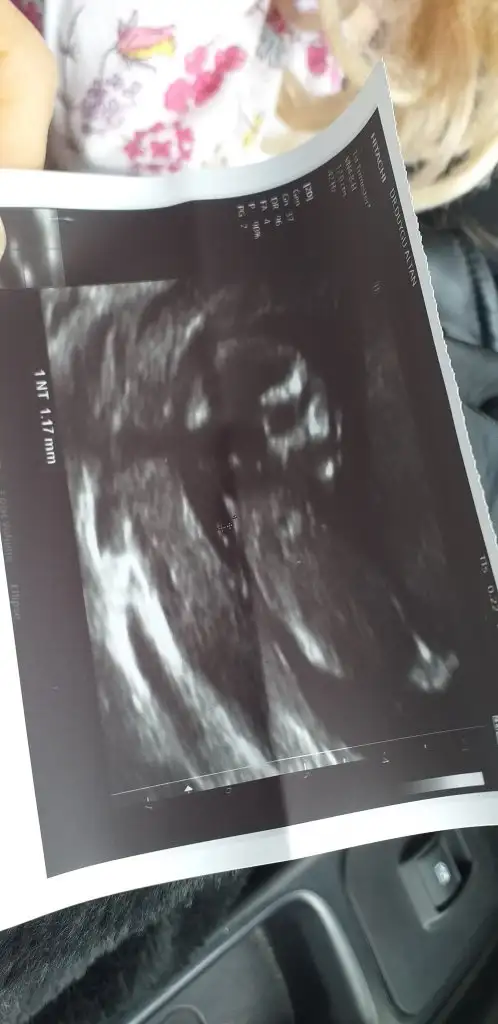

12 haftalik usg resmi bi.kucuk tahmin yokmuuÇok karanlık 11 12 13 haftalarda paylaşabilirsiiz

Meraba bizde 12 haftaligiz bu resimde bizede bi tahminde bulunurmusunuzŞimdiki usg ni atsana canım

Erkek olabilirMeraba bizde 12 haftaligiz bu resimde bizede bi tahminde bulunurmusunuz